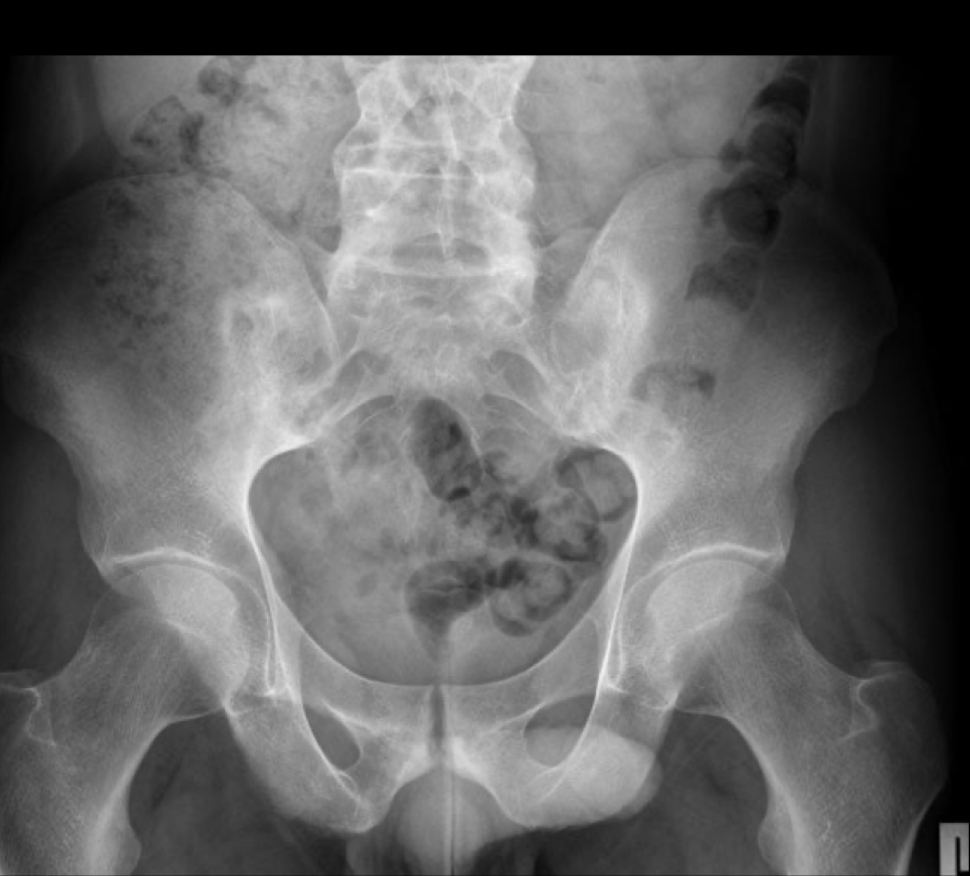

q se ve en rx y tc de sacroileitis?

A

poca sensibilidad

- Util en proceso cronico

- Esclerosis sacroiliaca : radiopacidad, se forma hueso

- Irregularidad y ensanchamiento